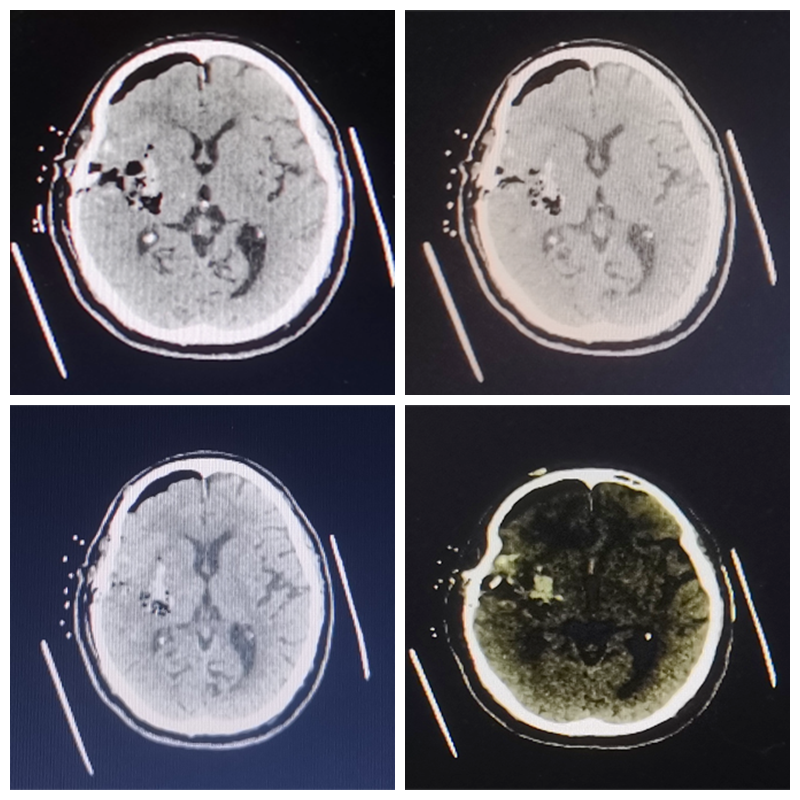

在征得家属及患者的同意后,手术团队决定为患者行神经内镜下脑内血肿清除术。手术顺利实施,术后复查颅脑CT血肿清除顺利,术后第1天患者神志即转清,经积极治疗后目前处于康复治疗中。

▲术后复查颅脑CT